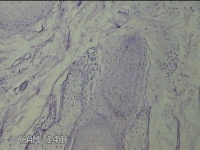

后颈部皮肤结节

性别

男

年龄

45岁

临床诊断

皮肤结节病

一般病史

发现后颈部皮肤结节半年余。

标本名称

大体所见

灰白粉红色组织1.7x0.9x0.3cm一块,表面带梭形皮肤1.7x0.9cm,皮下见结节1.5x1.1cm一个,切开结节呈实性,切面灰白粉红色,质软。

图2